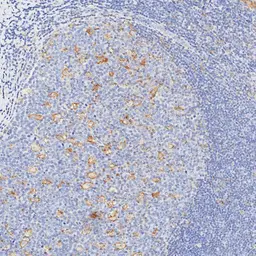

Optimal staining result of human tonsil using PD-L1 antibody [H302] HistoMAX™ on Leica Bond III, following the vendor recommended protocol settings.

Distinct punctate membranous reactivity (weak-to-moderate intensity) observed in germinal center macrophages and scattered lymphocytes. Note the high signal-to-noise ratio, with the predominant lymphocyte population remaining non-reactive.